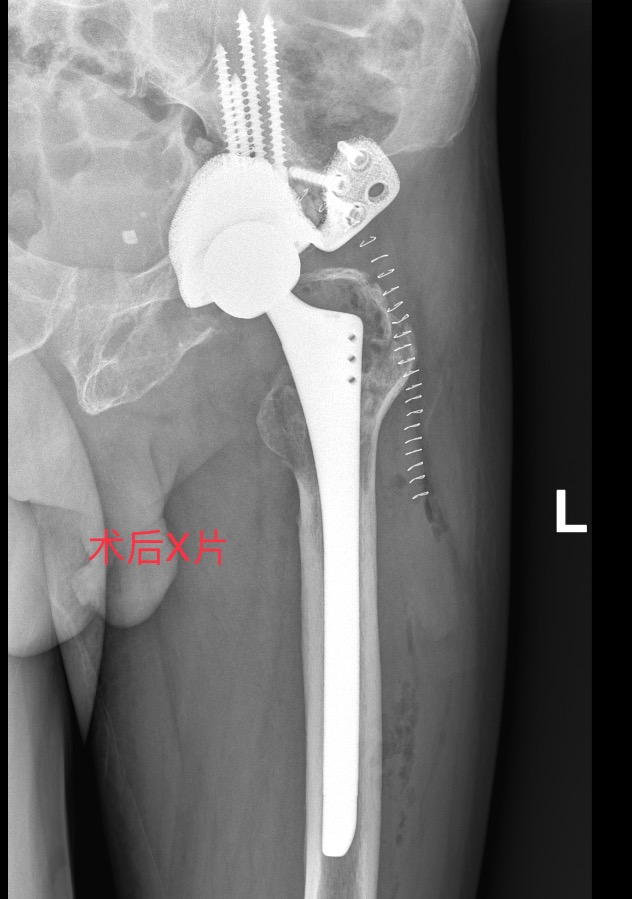

根据患者病情,考虑常规人工髋关节假体无法实现有效初始稳定性,而 3D 打印定制假体,能“量体裁衣” 般精准设计,突破常规手术局限,为曾爷爷量身打造独一无二的治疗方案,故选择3D打印个体化定制假体进行全髋关节翻修术。

我院骨伤中心与手术麻醉中心强强联合,组建 “硬核战队”,共同挑战这一全区首例的高难度手术。

麻醉苏醒后,曾爷爷的髋关节已能无痛自由屈伸;术后24小时内,借助助行器就能行走,生活起居已能完全自理!

2. 3D打印与定制化假体

根据患者骨骼形态打印假体,解决复杂骨缺损(如Paprosky IIIB型),实现“严丝合缝”的固定。

3. 生物材料升级

使用钛合金+羟基磷灰石涂层假体,促进骨长入,降低松动风险;抗菌涂层技术减少感染概率。

4. 微创与导航技术

3D打印导板辅助精准植入,缩短手术时间,减少出血和神经损伤风险。